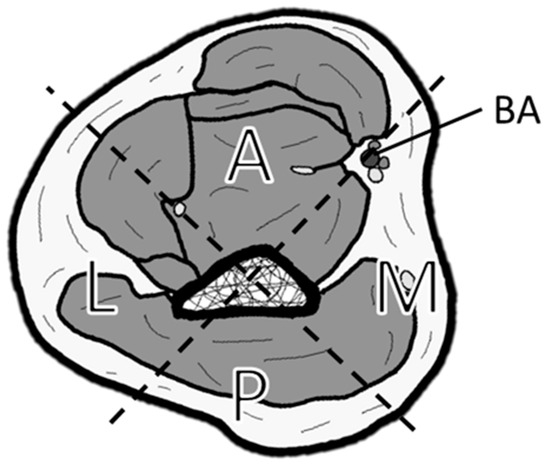

Figure 1.

Classification of soft tissue defect locations around the elbow. The elbow is divided into four zones by drawing a line connecting the center of the humerus and the brachial artery (BA), and a perpendicular line to it: A (anterior), M (medial), P (posterior), and L (lateral).

All patient and flap background data are presented in Table 1. Among the seven cases of elbow reconstruction, four were due to trauma, two were due to infection, and one was due to post-traumatic joint contracture. The locations of the free flaps were as follows: two were confined to the anterior region (A), one to the lateral region (L), one to the posterior region (P), one spanned the anterior and lateral regions (A and L), one spanned the anterior and medial regions (A and M), and one extended from the anterior to the medial and posterior regions (A, M, and P). The flap types used were ALT in four patients, LD in two, and a vascularized fibula graft (VFG) in one. The recipient vessels in all cases were the BA and its accompanying veins. In Case 1, where a VFG was performed in the lateral region (L), the short pedicle required adjusting the heel position during the anastomosis to relieve tension on the vascular anastomosis site (Figure 2F).

Understanding the characteristics of the BA and its suitability for various reconstructive sites and functions is crucial in recognizing the BA as a valuable recipient vessel in elbow reconstruction. The elbow’s intricate three-dimensional anatomy often requires reconstruction across multiple regions. The BA, positioned from the medial to the anterior aspect of the elbow, necessitates careful planning to prevent twisting of the flap pedicle during reconstruction. While vascular placement is straightforward in anterior and medial reconstructions due to the planar relationship between the flap and the BA, lateral and posterior reconstructions require three-dimensional positioning of the pedicle from the graft site to the anastomosis site. Surgical planning that considers the positional relationship between the flap and the BA is essential, especially when reconstructing in the posterior (P) or lateral (L) regions, as we demonstrated.